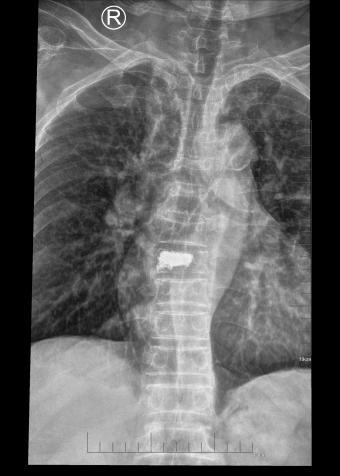

吴老太太今年86岁,同时患有心脏病、老慢支、哮喘、糖尿病等多种疾病,不久前因为并发心衰、呼衰在独墅湖医院经抢救后脱离危险。然而不巧的是,几天前自己在家只轻轻扭了一下腰,就感觉背部疼痛难忍,寝食难安。于是来到我院骨科就诊,医生怀疑是脊柱骨质疏松性骨折,安排收治住院,对病患进行磁共振检查后证实是“第8胸椎压缩性骨折”。

医生在诊断后决定行经皮椎体后突成形术(简称PKP术),需要病人在全身麻醉下俯卧位,医生在全程透视下完成手术。对于一般的患者来说不成问题,而对吴老太太而言却难以实施。首先,她的全身情况较差,心肺功能不全,基础疾病多且严重。入院时就有明显的呼吸困难,氧饱和度只有70%左右,很难耐受全身麻醉。即使勉强度过手术阶段,术后也可能要气管插管,靠呼吸机维持生命,肺部感染则难以控制。其次,如果采用局部麻醉俯卧位手术,尽管可以规避全麻的风险,但该患者根本不能承受俯卧位对心肺功能的影响。但如果不采取手术,卧床以及日夜不停的疼痛对已经遭受过心衰和呼衰的吴老太太来说是雪上加霜。